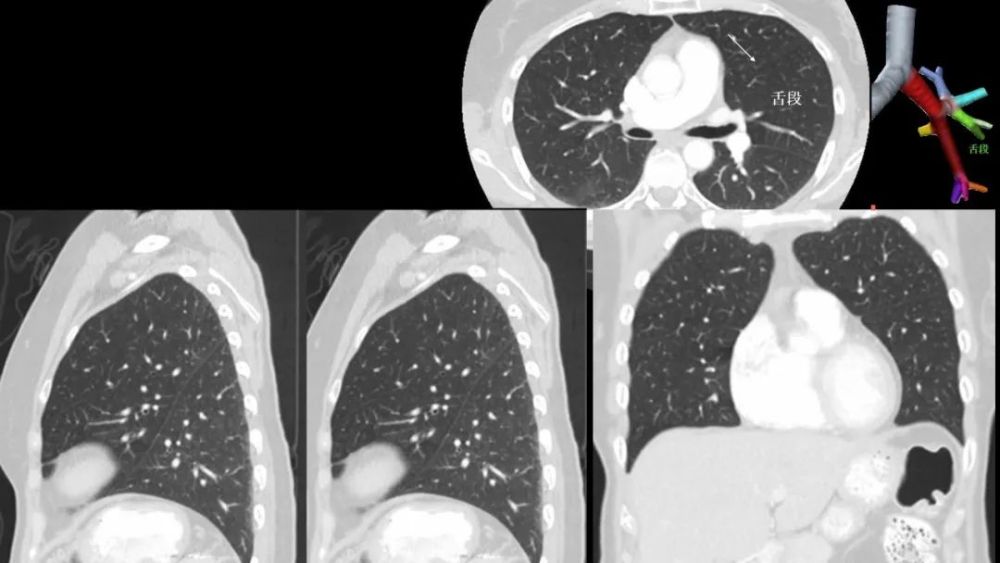

左侧水平裂

Left minor fissure

CT上的检出率为:8% , AP胸片为1.6%

左侧水平裂将舌叶从下叶其它部分分隔出来 舌叶仍然保留其上段和下段 , 不同于右肺中叶 内侧段和外侧段 , 因此左肺的段解剖保持完整